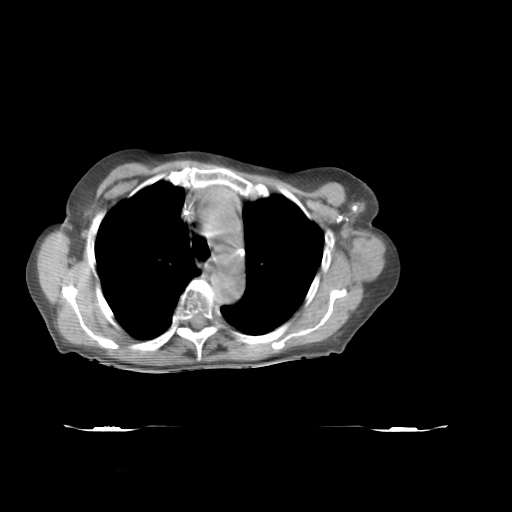

ClearRT® Images

Imaging Information

ClearRT®

Protocol

Thorax_Normal_50cm_medium

Scan Length

30 cm

KVCT Imaging Time

35 sec

Beam on Time

4.6 min